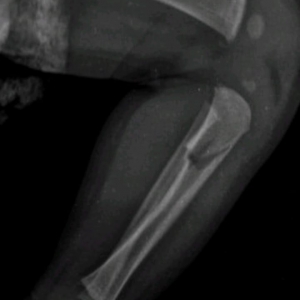

A criança, um menino, apresentava além de vários hematomas e escoriações pelo corpo, em exames aprofundados se constatou lesões ósseas em uma das tíbias, em um antebraço, além de costelas.

Laudo Médico apontou ainda que tais ferimentos expuseram o menino a risco de vida.